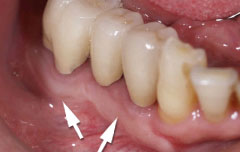

| 歯周病が進行したケースでは盲目下でポケット内の歯石を確実に除去するには限界があります。 | 局所麻酔をした後、歯茎を切開し、明視下にて歯根面の歯石や炎症組織を取り除き、歯周ポケットの除去をおこないました。 |